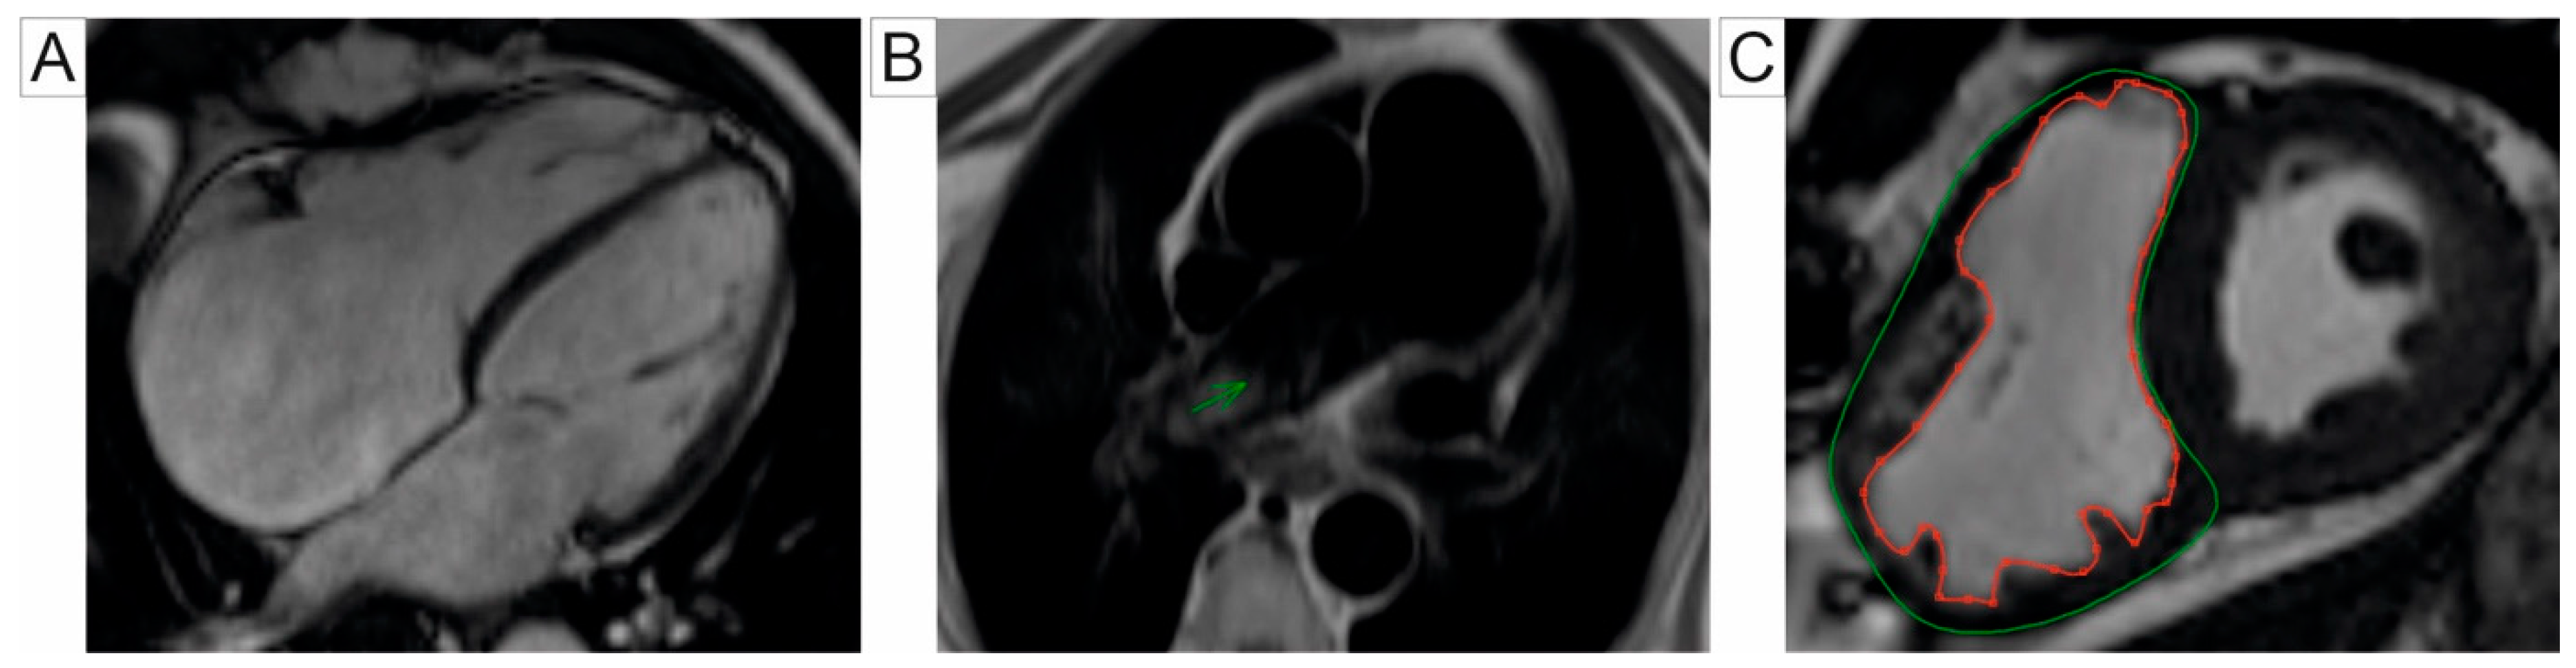

Phase-contrast (PC) CMR is a non-invasive imaging modality that quantifies blood flow and assesses haemodynamic changes by measuring blood velocity and volume flow in the PA, thus providing valuable insight into pulmonary circulation and right heart function [9]. The 2D-PC CMR facilitates a non-invasive analysis of PA stiffness through parameters such as pulse wave velocity (PWV). PWV reflects the compliance of the pulmonary vasculature and is typically measured using velocity maps of the PA obtained above the sigmoid valves. The transit time approach, which estimates the duration for a pressure wave to travel between two points in a vessel, is a commonly used method for PWV evaluation. However, its application is often restricted to the proximal PA due to the relatively short length of the vessel [43,44,45]. Bradlow et al. determined standard PWV values in healthy, non-smoking individuals, reporting 2.33 ± 0.44 m/s in the right PA and 2.09 ± 0.64 m/s in the left PA [45]. Combining high temporal resolution imaging with the flow-area method has demonstrated a superior accuracy and reproducibility for PWV measurements in the PA [46]. This methodology has shown particular promise in the pediatric population, as illustrated by Poon et al. [47]. CMR has shown a comparable accuracy to RHC in evaluating proximal PA stiffness, both at rest and during exercise. CMR has been effective in detecting early signs of arterial stiffness that may remain undetectable at rest, making it a valuable tool for an early identification of vascular changes in diseases such as PH [48,49]. The velocity transfer function (VTF), introduced by Gupta et al., represents a novel non-invasive method to assess PA impedance. VTF quantifies the relationship between flow velocity and pressure, serving as a reliable surrogate marker for PA stiffness and resistance [50]. This technique has particular relevance in PH patients with chronic obstructive pulmonary disease, as an increased mean high-frequency modulus (MHFM) of VTF is associated with impaired exercise tolerance and RV remodeling [51]. Although promising, additional validation studies are necessary to confirm the clinical utility of VTF as a diagnostic and prognostic marker. PH evaluation using 2D-PC CMR can be seen in Figure 3.

Four-dimensional flow CMR is an advanced imaging technique that encodes velocity across three spatial dimensions and time. This innovation overcomes the limitations of traditional 2D-PC CMR, echocardiography, as well as computer tomography (CT), which are less effective in accurately measuring blood flow velocities [10]. In addition to providing fundamental 2D hemodynamic data, 4D flow CMR allows advanced visualization tools such as streamlines to depict blood flow patterns (e.g., laminar, helical, or vortical flow) and velocity vectors. It also enables a quantitative analysis with metrics like WSS and flow energetics, which are predominantly used in research settings [10,52,53]. This technique has broad applications, offering valuable insights into energy distribution and blood flow in large vessels and the heart in both healthy individuals and patients with cardiovascular pathologies [10]. While its primary use lies in evaluating congenital heart diseases, 4D flow CMR has also proven beneficial in assessing PH and pulmonary valve disease [52,54]. In addition, its ability to detect early hemodynamic changes makes it particularly useful for patients with connective tissue disease, potentially enabling early diagnosis before the onset of PH [55,56]. Studies have demonstrated a good agreement between 2D and 4D flow CMR, with the latter showing superior accuracy in evaluating pulmonary flow, RV volumes, and function [57,58,59]. Specifically, 4D flow CMR provides more precise flow quantification through pulmonary valve tracking, making it the preferred method for patients with repaired Tetralogy of Fallot [57,58].

In PH, blood flow is typically irregular and turbulent, with disrupted circular patterns. Using the 4D-flow CMR, the visualization of vortex emergence within the PA vasculature is possible, serving as a valuable marker for identifying overt PH. CMR-based measurement of vortical blood flow duration in the PA trunk have been shown to accuratly estimate PAPm in resting states, enabling the non-invasive detection of PH, as suggested by Reiter et al. [63,64]. Their findings indicate that the vortical flow begins to emerge when PAPm exceeds 16 mmHg, with the duration of the vortex increasing proportionally to PAPm [63]. To differentiate the patients with PH from healthy subjects, Schafer et al. quantify helicity and vorticity in the PA. The authors found that helicity significantly decreased in the main pulmonary artery (MPA) and RPA, whereas vorticity decreased only in the RPA. Notably, these parameters showed no significant variability between the different PH subgroups. Among these markers, total helicity emerged as the non-invasive marker with the highest diagnostic precision [65]. Ramos et al. demonstrated that assessing the CMR-derived vortex duration offers superior diagnostic accuracy for tracking the PA pressure compared to the transtricuspidian gradient measurement obtained via a Doppler echocardiography [66]. Another approach to the quantifying vortex flow involves evaluating backward flow components, such as duration, volume flow rate, and cross-sectional area. Kamada et al. evaluated patients with PH due to CTEPH and concluded that these indicators are reliable for evaluating therapeutic outcomes, particularly after a balloon pulmonary angioplasty [67]. Figure 4 illustrates the PH assessment using 4D-flow CMR.